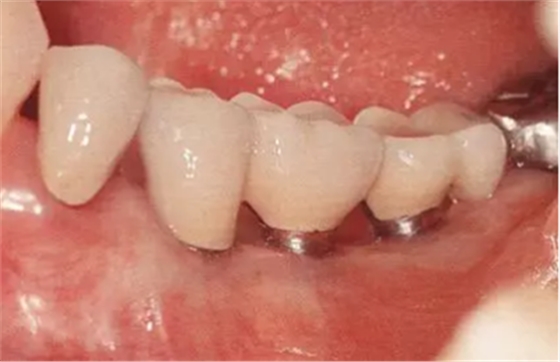

▲圖10-11,12

佩戴最終修復(fù)體后2年的狀態(tài)。頰舌側(cè)角化齦寬度均充足。

▲圖10-13,14

圖10-13 佩戴最終修復(fù)體后16年的狀態(tài)。

圖10-14 同時期的(牙合)面照。